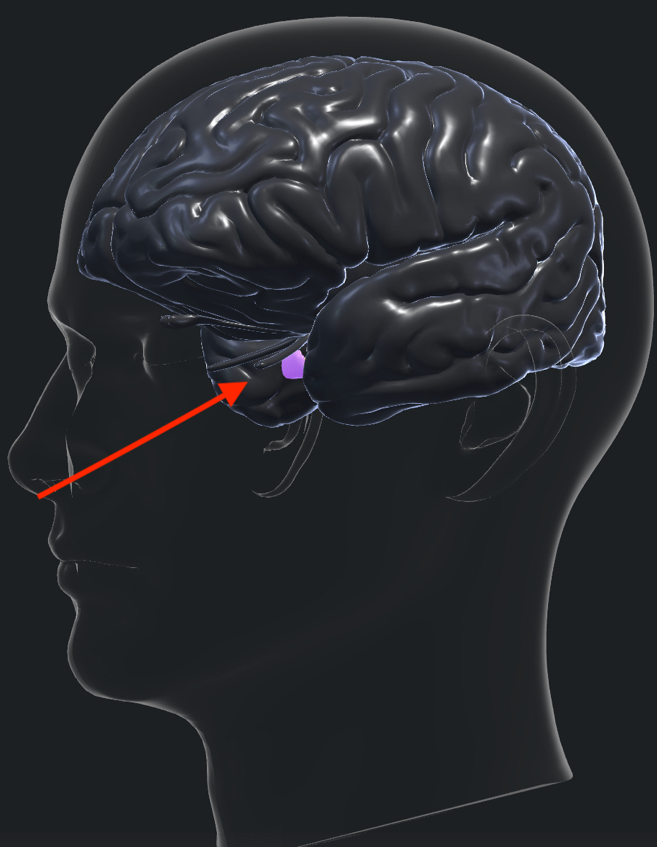

Η υπόφυση είναι ένας αδένας μεγέθους περίπου ενός κυβικού εκατοστού που εντοπίζεται γεωμετρικά στο κέντρο του κρανίου πάνω σε μια οστέινη βάση, που ονομάζεται το τουρκικό εφίππιο κοντά στο σημείο όπου διασταυρώνονται τα δύο οπτικά νεύρα. Είναι υπεύθυνη για τη σύνθεση και την έκκριση πολυάριθμων ορμονών, οι οποίες είναι απαραίτητες για την φυσιολογική λειτουργία του κεντρικού νευρικού συστήματος και του οργανισμού γενικότερα. Πιο ειδικά, η υπόφυση αποτελείται από: έναν πρόσθιο (αδενοϋπόφυση) και έναν οπίσθιο λοβό (νευροϋπόφυση). Ο οπίσθιος λοβός συνδέεται με τον μίσχο της υπόφυσης με τον υποθάλαμο, και αποθηκεύει τις ορμόνες που παράγονται εκεί, όπως τον ωκυτοκίνη και την αντιδιουρητική ορμόνη. Όταν είναι απαραίτητο, απελευθερώνει αυτές τις ορμόνες.

Τα κύρια συμπτώματα ενός αδενώματος της υπόφυσης απορρέουν είτε από την ανατομική τους θέση, που είναι πολύ κοντά στην ένωση των οπτικών νεύρων ή/και από τη λειτουργία τους, δηλ. την έκκριση των ορμονών.

Μία από τις πιο συνηθισμένες παθήσεις στο κρανίο στην οποία χρησιμοποιείται το ενδοσκόπιο είναι οι όγκοι του τουρκικού εφιππίου, όπως τα καλοήθη αδενώματα της υπόφυσης και τα κρανιοφαρυγγιώματα. Στις περιπτώσεις αυτές η είσοδος στο κρανίο γίνεται από την μύτη (Εικ. 1). Το ενδοσκόπιο παρέχει εξαιρετική απεικόνιση της περιοχής από τον βλεννογόνο της μύτης μέχρι και τον σφηνοειδή κόλπο και την περιοχή της υπόφυσης μετά το άνοιγμα του εδάφους του τουρκικού εφιππίου. Αντιπροσωπευτικές διεγχειρητικές φωτογραφίες φαίνονται στις εικόνες 2α,β,γ.